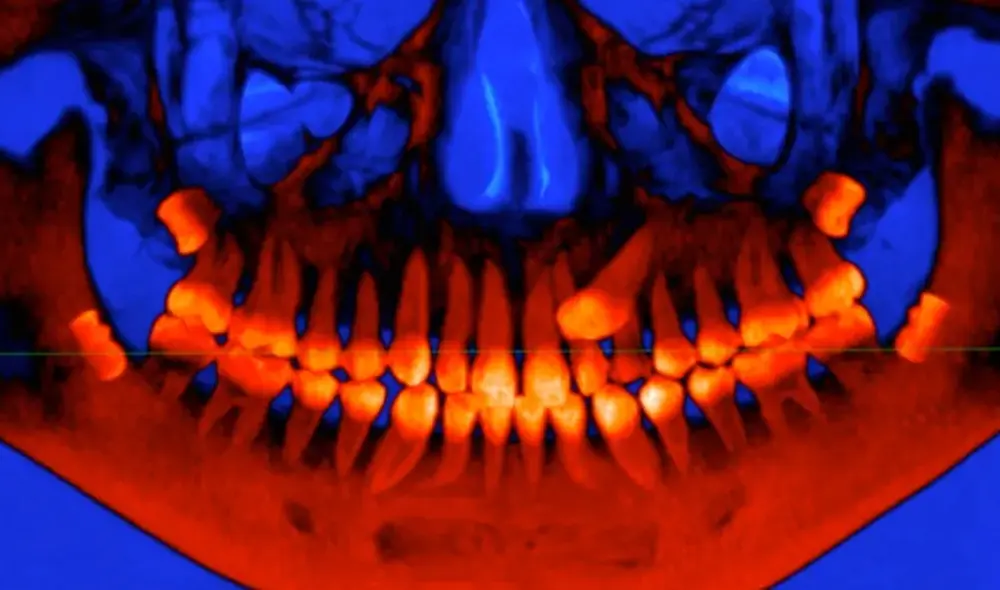

Luego de modelar cráneos en 3D de 21 especies de primates, los investigadores descubrieron que la sincronización de nuestros molares adultos tiene relación con el delicado equilibrio de las articulaciones del cráneo en crecimiento.